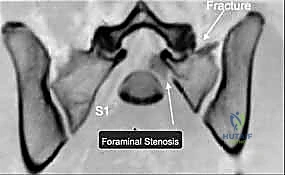

يمر عبر عظم العجز جذور الأعصاب العجزية التي تتحكم في وظائف حيوية مثل حركة الأطراف السفلية، التحكم في المثانة، ووظائف الأمعاء. أي انزياح عظمي في هذه المنطقة قد يؤدي إلى قطع أو انضغاط هذه الأعصاب، مما يسبب إعاقة دائمة إذا لم يتم تحريرها وتثبيت الكسر بدقة متناهية بواسطة خبير مثل الأستاذ الدكتور محمد هطيف.

3. التصوير المقطعي المحوسب (CT Scan): وهو المعيار الذهبي (Gold Standard) لتشخيص كسور الحوض والعجز. يقوم الدكتور هطيف باستخدام تقنية إعادة البناء ثلاثي الأبعاد (3D Reconstruction) لفهم هندسة الكسر بدقة متناهية قبل الدخول إلى غرفة العمليات.